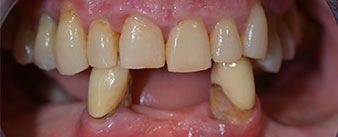

Die 64-jährige Patientin wurde mit einer Unterkiefer-Restbezahnung 38, 33 und 43 und einer klammerbefestigten Interimsprothese im Unterkiefer vorstellig (Abb. 1 und 2).

Die notwendige parodontologische Behandlung und Extraktion im Oberkiefer sollte zu einem späteren Zeitpunkt erfolgen, da die Patientin Lehrerin ist und zu dem Zeitpunkt mit Abiturprüfungen beschäftigt war. Sie konnte weder essen noch adäquat sprechen, da die Interimsprothese sehr häufig und bei der kleinsten Belastung brach.